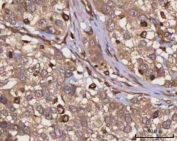

IHC staining of FFPE human rectum adenocarcinoma tissue with PPP3CB antibody. HIER: boil tissue sections in pH8 EDTA for 20 min and allow to cool before testing.

IHC staining of FFPE human urothelial carcinoma tissue with PPP3CB antibody. HIER: boil tissue sections in pH8 EDTA for 20 min and allow to cool before testing.